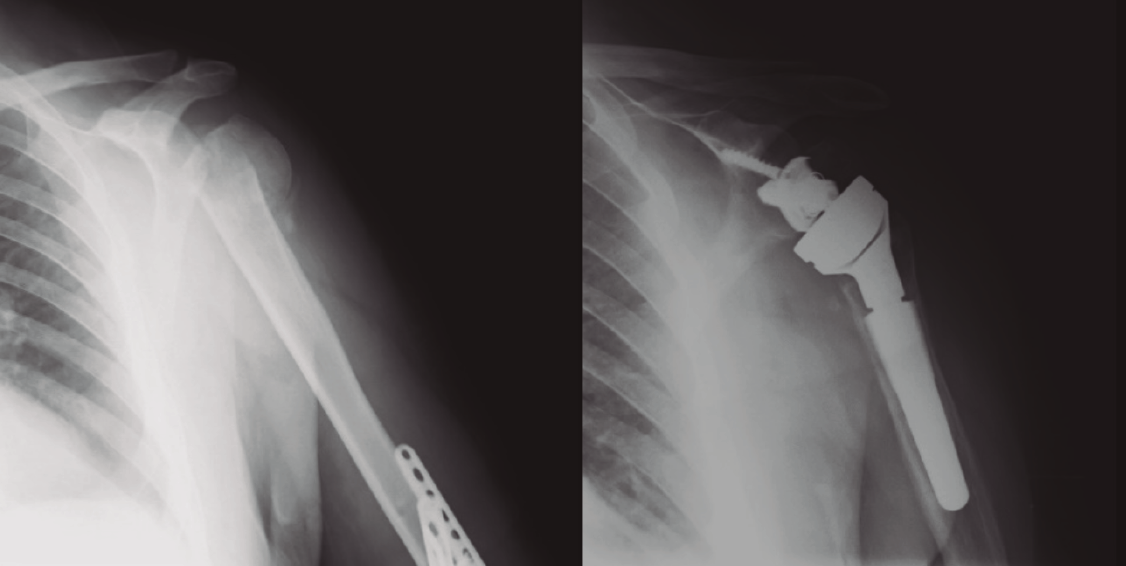

Protocolo rehabilitador tras la implantación de prótesis invertida total de hombro (Tabla 2 y Figura 9)

Figura 9. Radiografía de una fractura de húmero pre- y posprótesis invertida.